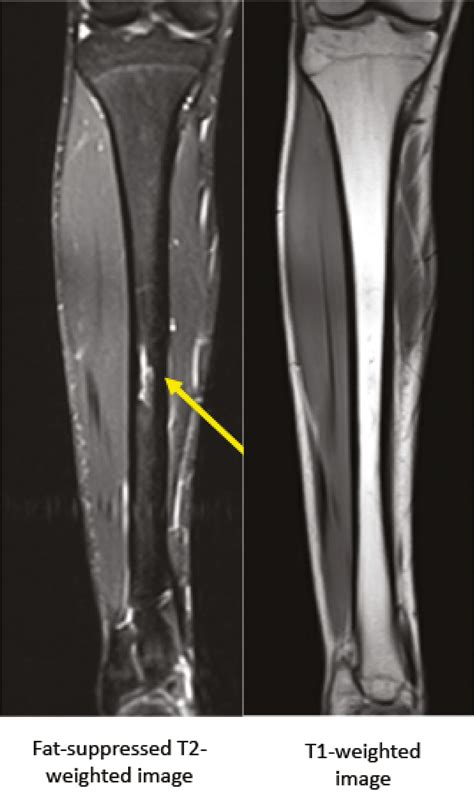

Doctors may suggest more sensitive imaging techniques if clinical symptoms remain high despite a clear X-ray. An MRI is often considered the "gold standard" for diagnosing a stress fracture tibia because it can detect bone marrow edema (swelling inside the bone), which is an early sign of stress-related injury before a fracture line even forms.